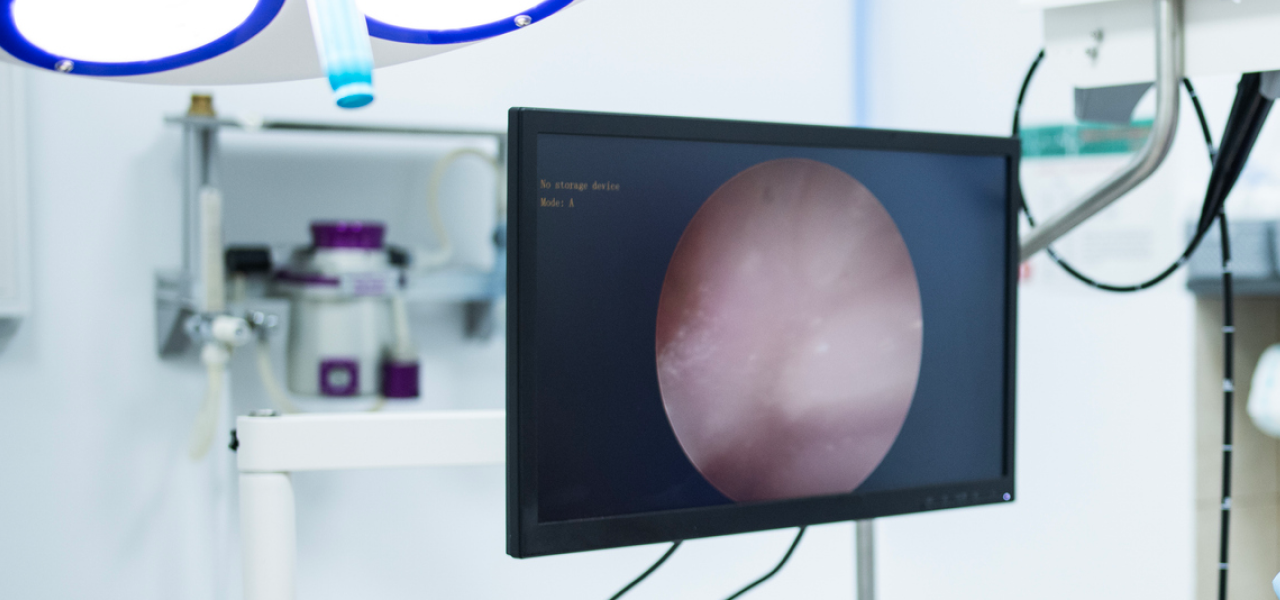

소화기 질환의 원인을 정확히 파악하기 위해 내시경 검사가 필요할 수 있습니다.

특히, 단순한 초음파·X-ray 검사로는 확인하기 어려운 위·장 내부의 미세한 염증, 궤양, 종양 등을 직접 확인할 수 있습니다.

상부·하부 내시경 검사를 통해,

보이지 않는 병변까지 정확히 진단합니다.

X-ray, 초음파로 확인할 수 없는 위·장 내부 병변까지 직접 확인할 수 있습니다.

상부 내시경 검사 : 위, 식도, 소장의 염증, 궤양, 이물질 확인

하부 내시경 검사 : 대장·소장의 염증, 종양, 만성 질환 평가

필요 시 조직검사를 진행하여, 보다 정밀한 병리 분석 제공